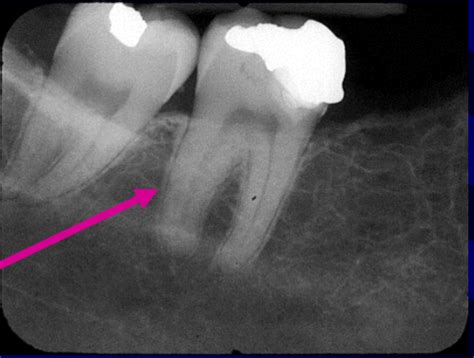

First up, we have radiographic density. This refers to the degree of blackness on a radiograph. The denser the structure, the more X-rays it absorbs, resulting in a lighter (or more radiopaque) appearance on the image. Conversely, less dense structures allow more X-rays to pass through, leading to a darker (or more radiolucent) appearance. Bone, for example, is quite dense due to its high calcium content, making it appear bright on a radiograph. Air, on the other hand, is much less dense, resulting in darker areas. Understanding radiographic density is fundamental to interpreting radiographs accurately. Variations in density can indicate the presence of abnormalities, such as tumors or fractures. Factors affecting density include the thickness of the tissue, its composition, and the energy of the X-ray beam. In clinical practice, adjusting technical factors like kVp and mAs allows us to optimize radiographic density for different body parts and diagnostic purposes.

Next, let’s talk about contrast. Radiographic contrast is the difference in density between adjacent structures on a radiograph. High contrast means there’s a significant difference in density, making it easier to distinguish between structures. Low contrast, on the other hand, makes it difficult to differentiate between tissues. Contrast is influenced by factors such as the energy of the X-ray beam (kVp), the type of tissue being imaged, and the use of contrast agents. For instance, imaging soft tissues often requires the use of contrast agents to enhance visibility. These agents, like barium or iodine, increase the density of specific structures, making them more visible. Proper contrast is essential for detecting subtle abnormalities and ensuring accurate diagnoses. Radiologists carefully adjust technical factors and contrast agents to achieve the optimal level of contrast for each specific examination.